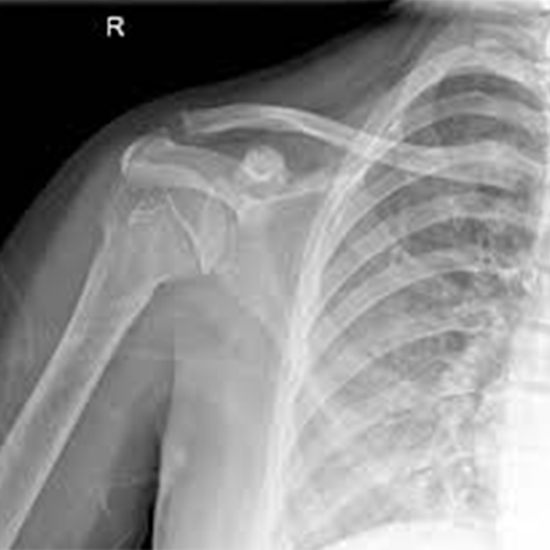

X-Ray Right Shoulder Joint AP

Book X-Ray Right Shoulder Joint AP Appointment Online Near me at the best price in Delhi/NCR from Ganesh Diagnostic. NABL & NABH Accredited Diagnostic centre and Pathology lab in Delhi offering a wide range of Radiology & Pathology tests. Get Free Ambulance & Free Home Sample collection. 24X7 Hour Open. Call Now at 011-47-444-444 to Book your X-Ray Right Shoulder Joint AP at 50% Discount.

The shoulder joint can be visualized using an X-ray. The shoulder includes the shoulder joint, collar bone, shoulder blade, upper arm bone, and surrounding skin and muscles.